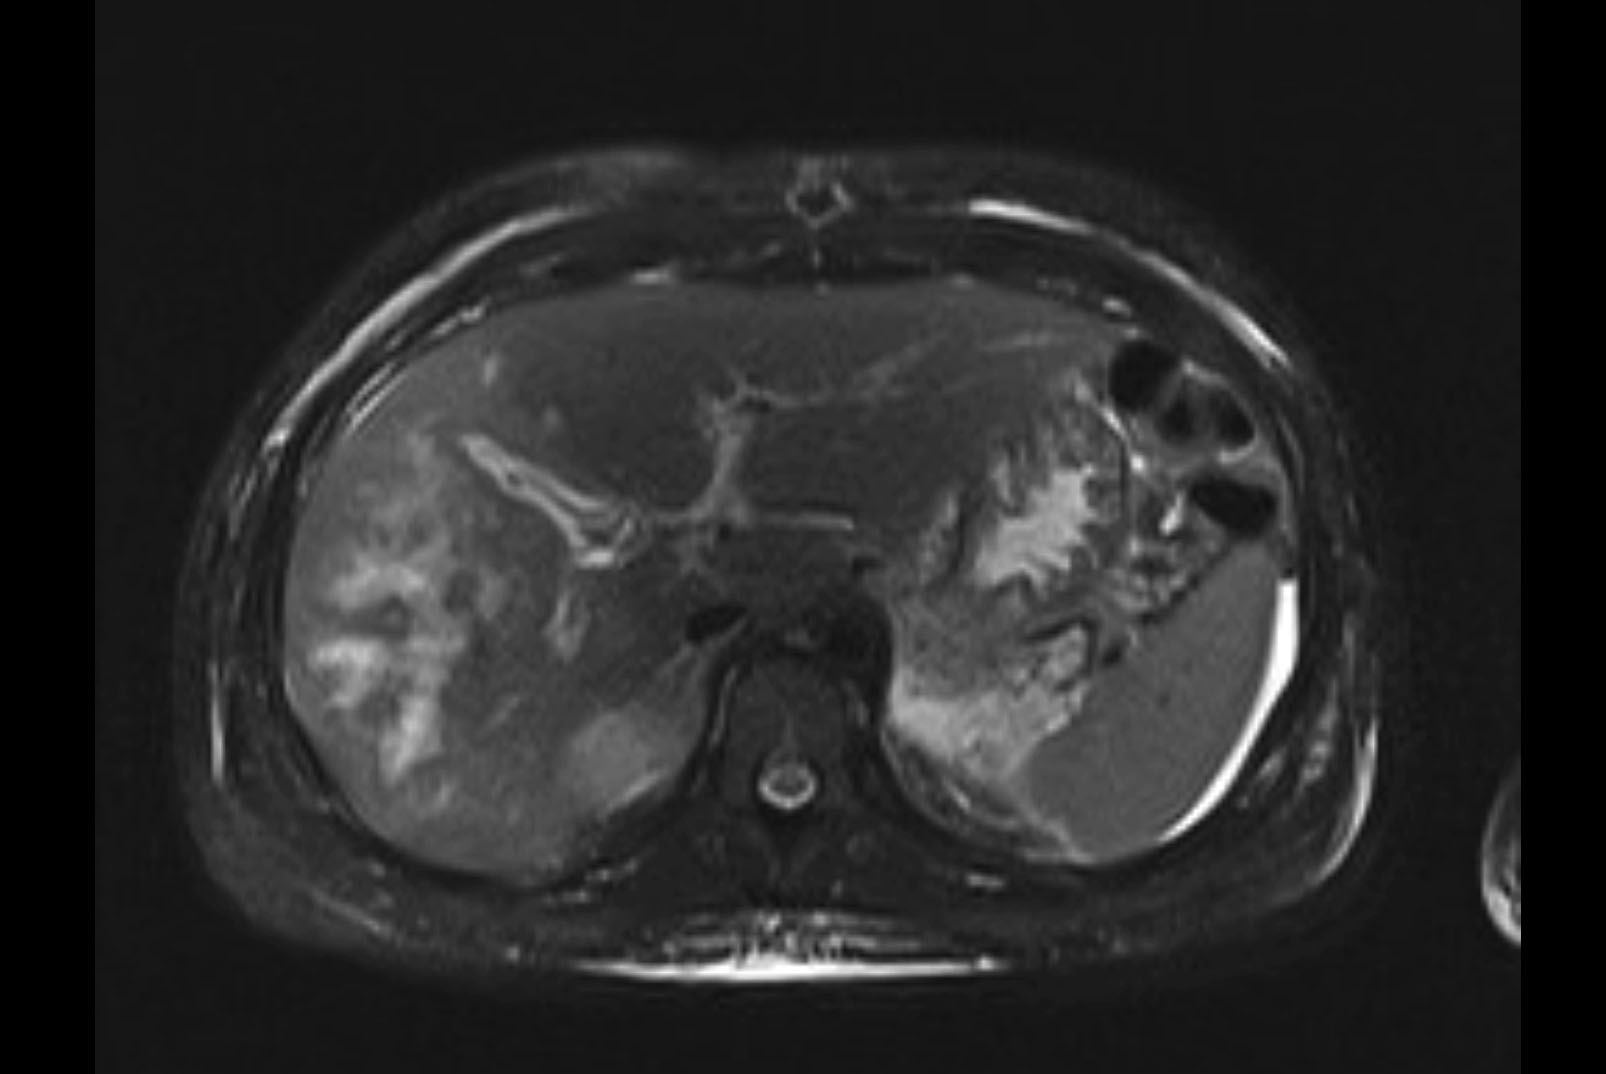

MRI T1

MRI T2

Imaging analysis

Based on initial findings, which issue(s) would you be most concerned about?